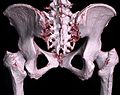

Jedes Pixel in einem Schnittbild entspricht einem Volumenelement (Voxel) des gesamten dreidimensionalen Datensatzes. Die Höhe des Voxels entspricht dabei der Schichtdicke. In der Nachbearbeitung lassen sich aus den Voxeln beispielsweise beliebig im Raum angeordnete Schichtbilder (multiplanare Rekonstruktion, MPR), geschichtete (Subvolumen-)Maximumintensitätsprojektionen (MIPs) oder dreidimensionale Bilder des untersuchten Objekts (Volumenrendering) errechnen.

3D-Rekonstruktion (Volumenrendering) des Beckens aus einem CT-Scan -